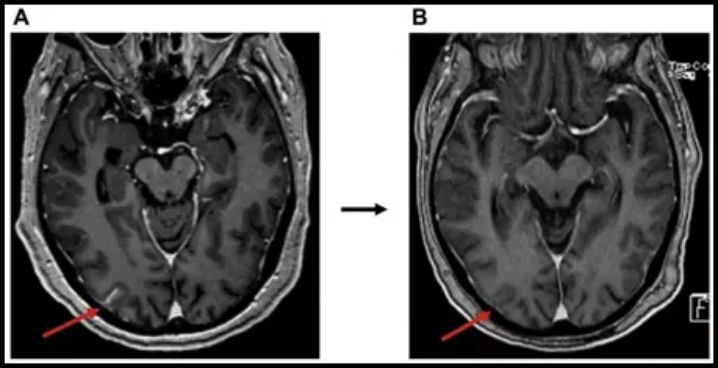

②有症状的脑转移(配合脑转移处理,如全脑放疗、培美曲赛、替莫唑胺、鞘内注射等);③有症状的全身性(颅外)孤立性病灶(转移灶<3-5个)。